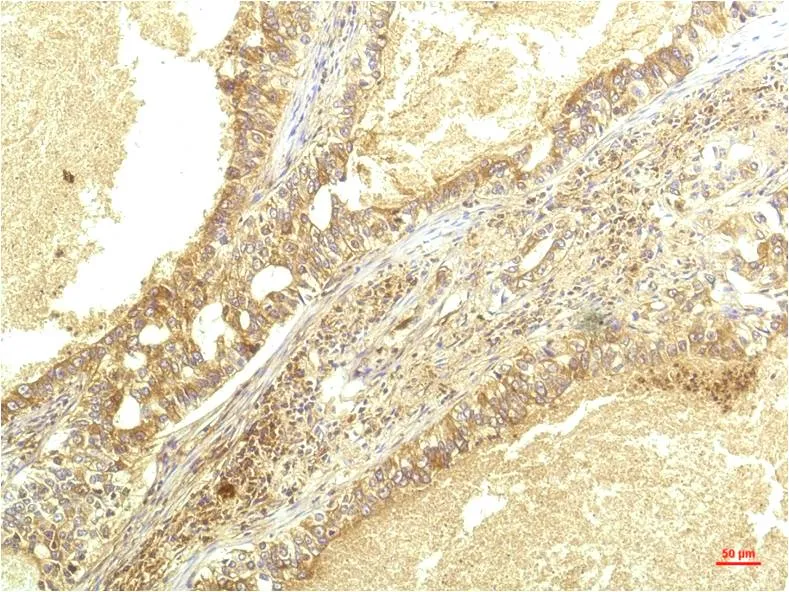

JAK1 (8D8) Mouse Monoclonal Antibody

Cat: AMM00786

Application:IHC-P

Reactivity:Human,Rat,Mouse

Conjugate:Unconjugated

Gene Name:JAK1